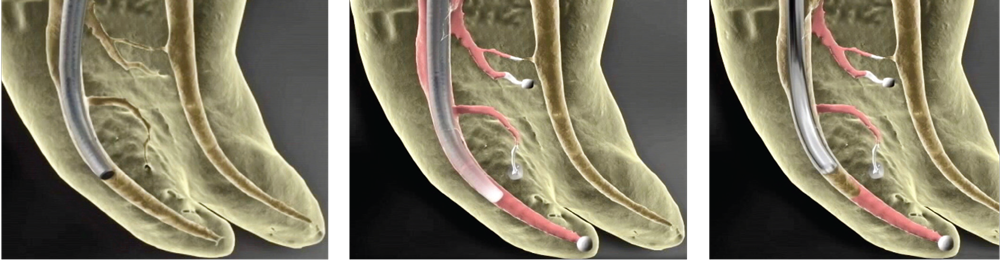

Fig. 1a (left): Continuous wave (CW) electric heat plugger being fitted before cementation of gutta percha and downpack. Fig. 1b (center): CW plugger at apical extent of the downpack. Fig. 1c (right): Backfill gap between apical mass of gutta percha at canal diameter of 0.4mm and the 0.65mm diameter of a 23 Ga. backfill cannula.

Continuous wave obturation, with its dead-soft stainless steel electric heat pluggers (Elements Free by Kerr Endodontics) and its nickel titanium hand pluggers (Buchanan Pluggers, also by Kerr), enables clinicians to downpack within 4–6mm of the end of most any small, curved canal—a huge improvement over the Schilder technique with its rigid pluggers. However, the CW technique, as done with traditional sealers, requires prefitting the electric heat pluggers in the canals before cementing the master cone in the canal with sealer.

This prefitting routine is done by pressing the appropriate-sized plugger into the canal as it is rocked back and forth. This rocking action causes the plugger to work its way into the canal; in the process, the canal very accurately bends them to match its curvature (Fig. 1a). It was this improvement that enabled a much deeper downpack than the Schilder Warm Vertical Technique, while filling all lateral canals in less than 2?seconds (Fig. 1b).

Change 21 percent shrinkage to 0.2 percent expansion, and suddenly nobody cares how thick the sealer layer is; we only care if we can move it into all the lateral irregularities that have been cleaned out. Combine net expansion on setting with extremely low surface tension and high wettability,40 and suddenly we find that a downpack of just 3–4mm will fill every nook and cranny in the most complicated anatomy. This pivot in the continuous wave obturation procedure simplifies the downpack, because electric heat pluggers no longer need to be prefitted and bent before cementing master cones. This reduced need to achieve depth in the downpack also means it is much easier to backfill without voids.